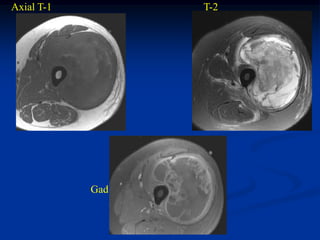

Case #250.2                Coronal T-1 MRI

45 year female with desmoid tumor gluteus maximus

Axial T-1 MRI

Axial T-2 MRI